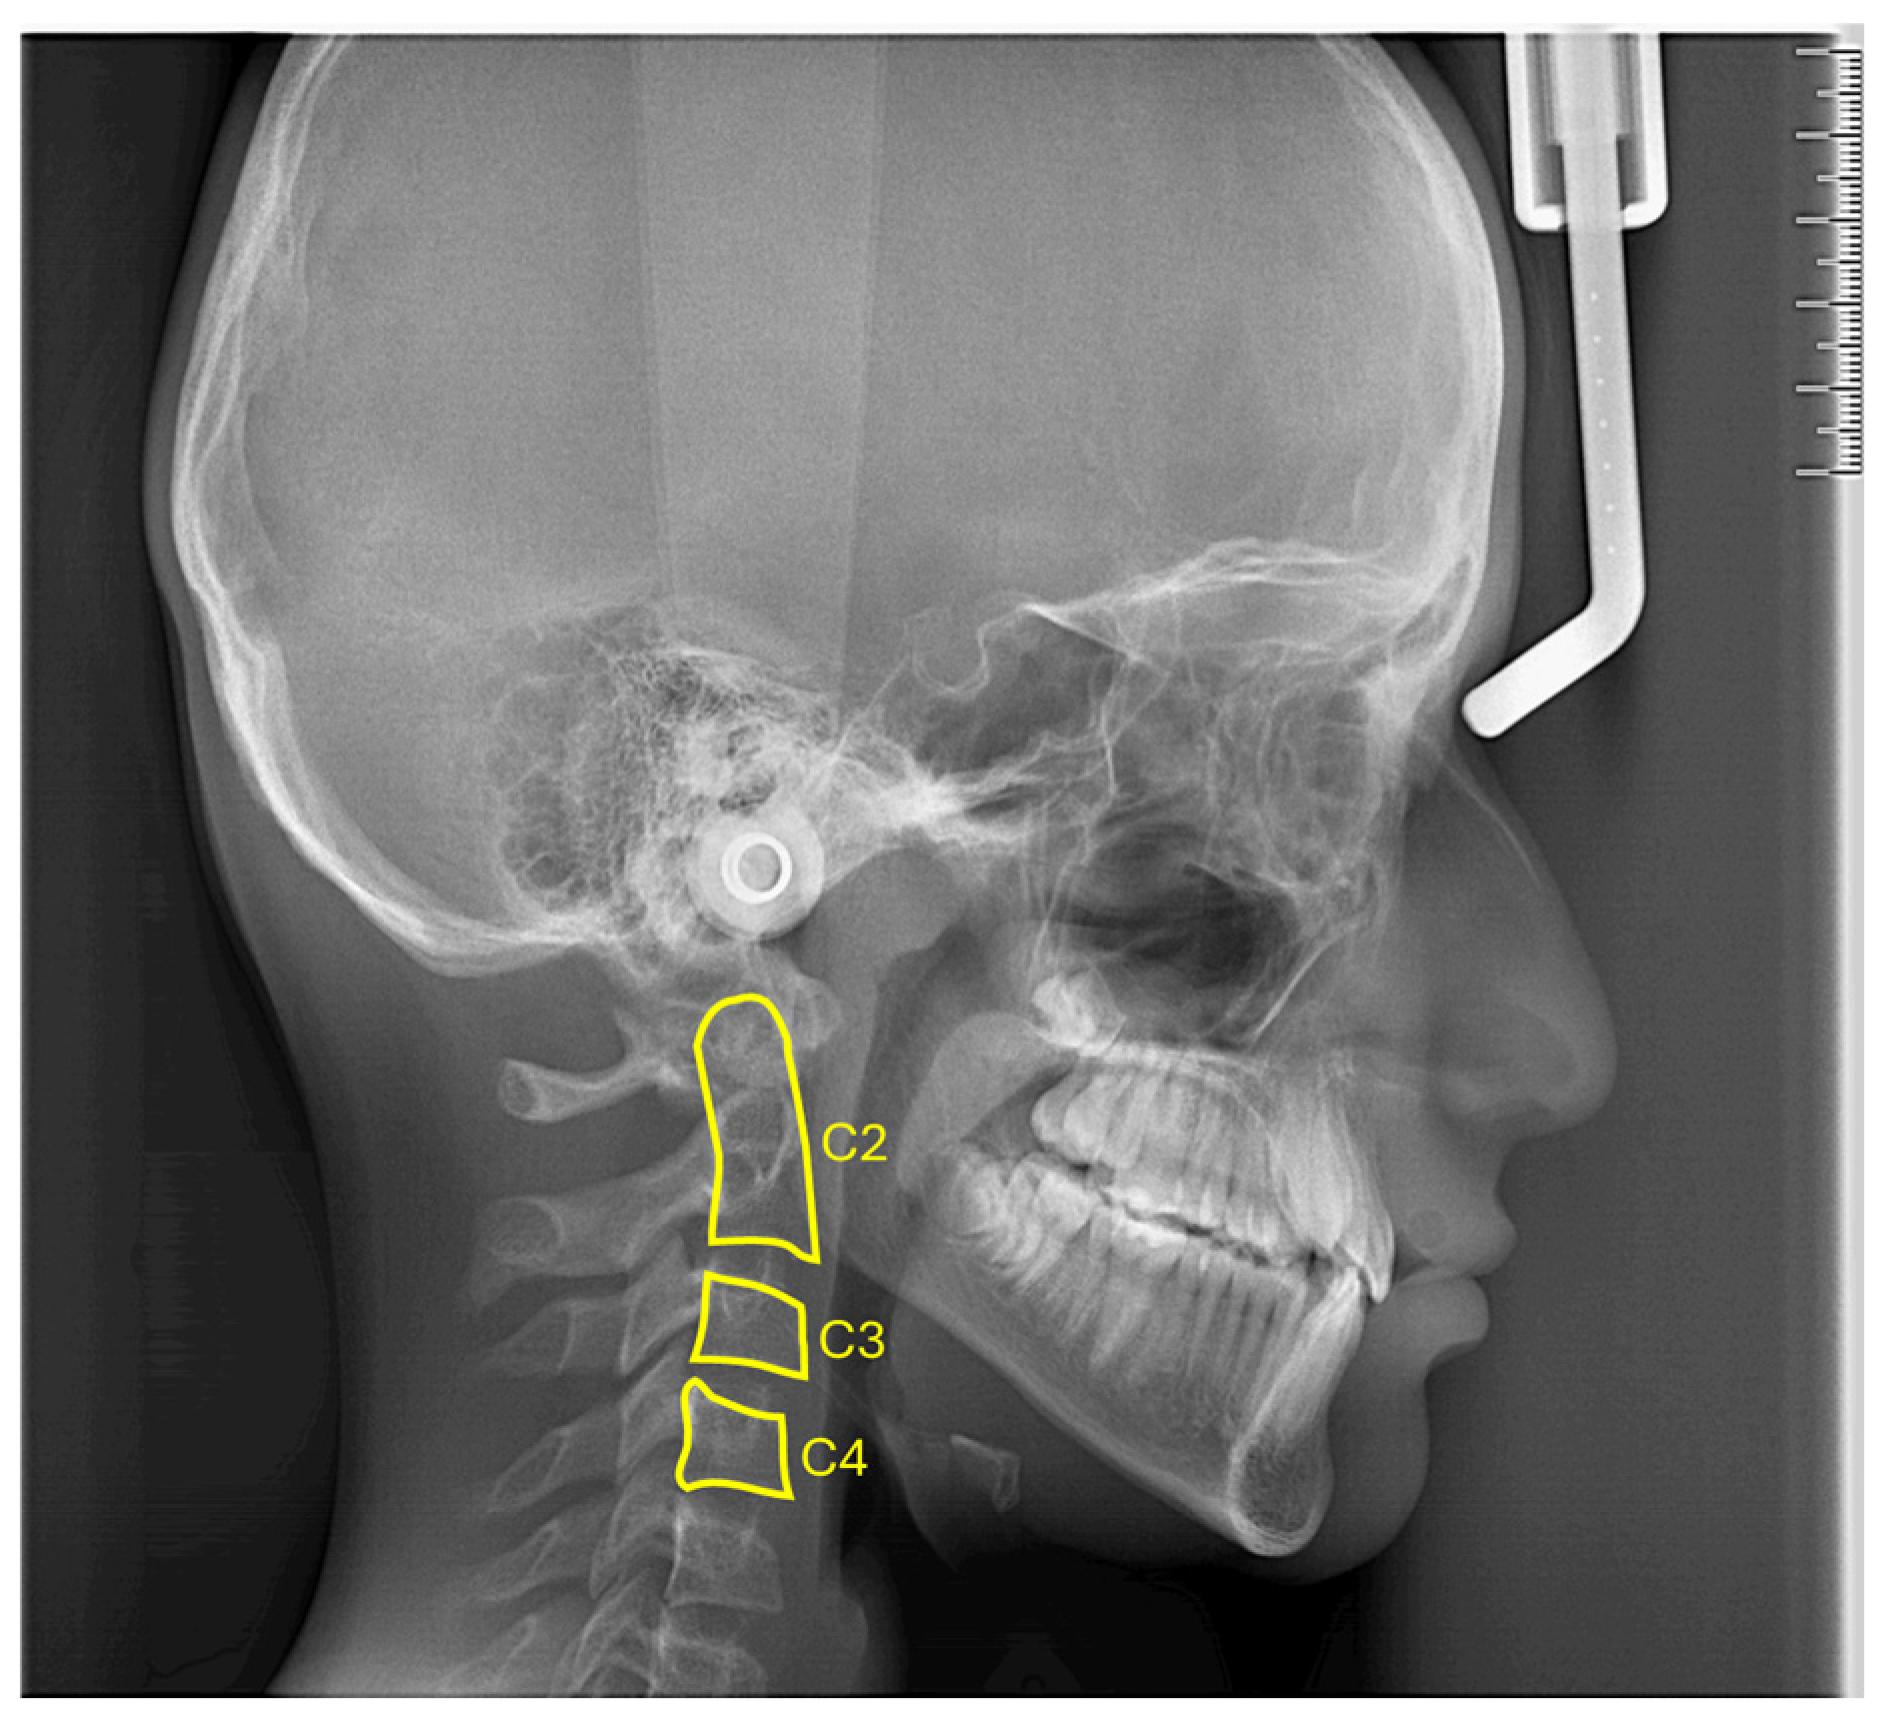

Accurate identification of growth and development stages is critical for orthodontic diagnosis, treatment planning, and post-treatment retention. While hand–wrist radiographs are the traditional gold standard, the associated radiation exposure necessitates alternative imaging methods. Lateral cephalometric radiographs, particularly the maturation stages of the second, third, and fourth cervical vertebrae (C2, C3, and C4), have emerged as a promising alternative. However, the nonlinear dynamics of these images pose significant challenges for reliable detection. This study presents a novel approach that integrates chaotic functional connectivity (FC) matrices and fractal dimension analysis to address these challenges. The fractal dimensions of C2, C3, and C4 vertebrae were calculated from 945 lateral cephalometric radiographs using three methods: fast Fourier transform (FFT), box counting, and a pre-processed FFT variant. These results were used to construct chaotic FC matrices based on correlations between the calculated fractal dimensions. To effectively model the nonlinear dynamics, chaotic maps were generated, representing a significant advance over traditional methods. Feature selection was performed using a wrapper-based approach combining k-nearest neighbors (kNN) and the Puma optimization algorithm, which efficiently handles the chaotic and computationally complex nature of cervical vertebrae images. This selection minimized the number of features while maintaining high classification performance. The resulting AI-driven model was validated with 10-fold cross-validation and demonstrated high accuracy in identifying growth stages. Our results highlight the effectiveness of integrating chaotic FC matrices and AI in orthodontic practice. The proposed model, with its low computational complexity, successfully handles the nonlinear dynamics in C2, C3, and C4 vertebral images, enabling accurate detection of growth and developmental stages. This work represents a significant step in the detection of growth and development stages and provides a practical and effective solution for future orthodontic diagnosis.

Hand and wrist radiographs have long been considered the gold standard for determining skeletal maturation. These radiographs provide detailed information on the developmental status of the hand and wrist bones, allowing clinicians to identify critical growth stages [5]. However, concerns about cumulative radiation exposure, particularly in younger patients undergoing multiple radiographic imaging sessions, have led to interest in alternative methods. The morphologic analysis of the cervical vertebrae visible in lateral cephalometric radiographs offers an attractive solution by allowing the evaluation of skeletal maturation. This technique focuses on the visual assessment of morphological changes in the shape of each cervical vertebrae, second (C2), third (C3), and fourth (C4), as reliable indicators of growth and developmental stages. By utilizing radiographs already used in routine orthodontic evaluations, the CVM method minimizes additional radiation exposure while maintaining diagnostic accuracy [6,7].

Step 1: In the data preparation phase, 30 × 30 pixel images centered on the C2, C3, and C4 vertebrae bodies are extracted from two-dimensional lateral cephalometric radiographs taken during the pre-peak, peak, and post-peak skeletal growth stages. These images are used for orthodontic purposes to identify skeletal growth and development stages. The dataset is then split into 90% training data and 10% test data to ensure independence between the subsets.

The dataset used in this study was prepared experimentally at Zonguldak Bülent Ecevit University, Faculty of Dentistry, Department of Orthodontics. Specifically designed for the classification of pre-peak, peak, and post-peak growth and development stages, the dataset was derived from lateral cephalometric radiographs. To focus on the regions relevant to the classification task, the areas containing the C2, C3, and C4 vertebrae were isolated and cropped, as illustrated in Figure 2. This targeted approach ensured that the dataset emphasized the anatomical structures essential for growth and development stage analysis. The dataset was divided into three distinct classes: pre-peak, peak, and post-peak growth stages. As shown in Figure 3, each class included images of the C2, C3, and C4 vertebrae. For each vertebrae type, 315 images were included per stage, resulting in a total of 945 images for each stage and 2835 images for the entire dataset. The balanced distribution across classes ensured that all vertebral types were equally represented, minimizing bias and improving stage classification accuracy.

In addition to analyzing each vertebrae type individually, the study also evaluated the correlations between the C2, C3, and C4 vertebrae. This approach allowed a comprehensive analysis of the functional connections between the vertebrae, providing valuable insights into the differences between growth stages. By considering all vertebrae types together, the dataset enabled a holistic classification strategy that exploited the relationships between 945 vertebrae images at each stage. For model training and testing, the dataset was randomly divided into two independent subsets. About 90% of the images were used for training, while the remaining 10% were reserved for testing. To reduce computational complexity and streamline the fractal dimension analysis, all vertebrae images were cropped to a uniform size of 30 × 30 pixels, with the cropping centered on the vertebral regions of interest. This pre-processing step preserved critical features while increasing computational efficiency.

The inclusion criteria for lateral cephalometric radiographs are as follows: (i) lateral cephalometric radiographs taken in a natural head position and belonging to the pre-peak, peak, and post-peak growth and development stages; (ii) high-resolution lateral cephalometric radiographs that clearly show the second to fourth cervical vertebrae (C2, C3, and C4); and (iii) the absence of any congenital or developmental deformity or systemic bone disease of the vertebrae. Radiographs with poor image quality that did not meet at least one of these criteria were excluded from the study.